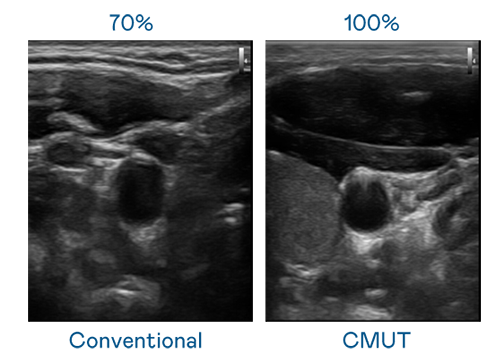

CMUT technology utilizes capacitive MEMS components to generate ultrasound signals. Compared to traditional ceramic piezoelectric technology, the 30% increased bandwidth of CMUT allows for wider ultrasound signals and greatly improved image resolution. This is a crucial technology for achieving medical ultrasounds with high-quality images and promoting the development of precision medicine.

The image quality of medical ultrasound depends on the signal bandwidth the ultrasound transducer can emit. AUO's CMUT offers high-resolution ultrasound signals with ultra-wide bandwidth and high sensitivity for more delicate image texture and details to help ultrasound medical examiners reduce time on interpreting and diagnosing based on precise medical images.